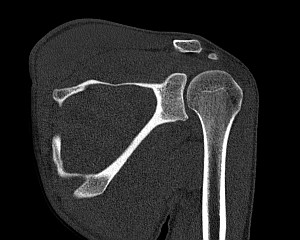

Плечевой сустав